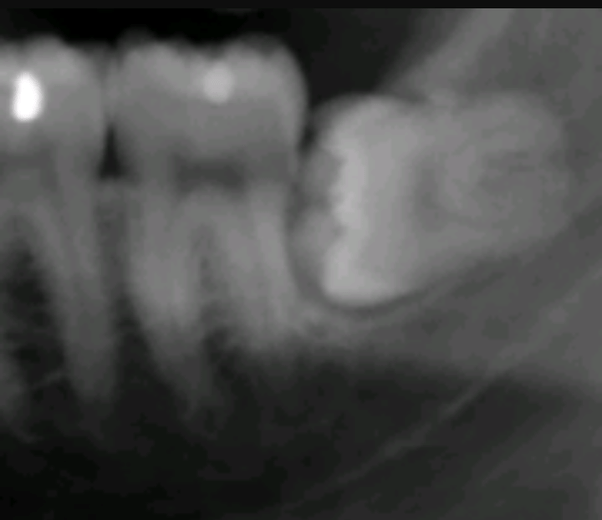

Extra Wisdom Tooth Coming In Under Molar Logy. Bottom wisdom tooth never came in. Had molar pulled a few years ago & now having jaw, ear pain, sore swollen gum where wisdom tooth is under gum.

Impacted wisdom teeth that grow horizontally happens due to spacing issues within your mouth. Grab the tooth with forceps. The one of the cause of uneruption of third molars is lack of space in jaw while developing and hence they become impacted.

Dear , the determination of whether the second molar needs to be extracted depends on the location and extent of the tooth decay. Dentist informed me she would. This step involves an instrument that get get underneath of the tooth and get it out by using leverage.